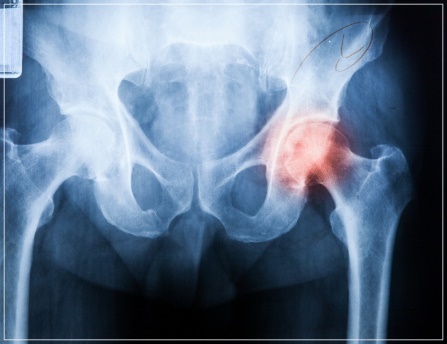

이상근증후군은 원인이 불분명한 데다 MRI 검사로도 이상 증상을 발견하기 어렵고 다른 검사법도 없어 진단이 어렵습니다. 통증의 양상과 임상경험을 통해 이상근증후군을 의심하고 치료를 하면서 진단하며 염증 완화나 근육을 부드럽게 하는 약물을 이상근에 주사했을 때 증상이 호전되면 이상근증후군으로 확진하게 됩니다. 이상근증후군의 정확한 진단을 내리기까지 시간이 걸리지만 증상이 의심되면 치료를 하면서 진단을 받는 것이 최선입니다.